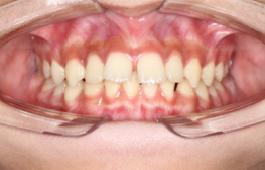

❸ 牙齿不齐:影响咬合关系,影响美观。

前

后